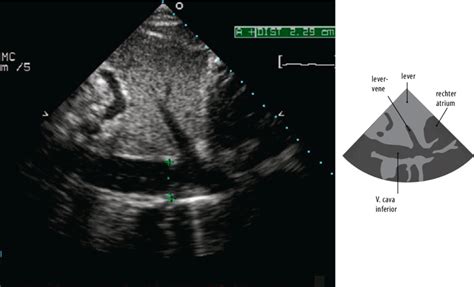

Op dag 10 is het embryo nog geen halve centimeter groot. De kans om het op een echo te vinden is dan slechts 70%. Vier tot vijf dagen later, rond dag 14 tot 16, is het embryo uitgegroeid tot een ongeveer twee centimeter groot, met vloeistof gevuld bolletje. Dit bolletje is goed herkenbaar op de echo, vandaar dat de meeste drachtigheidscontroles rond deze periode plaatsvinden.